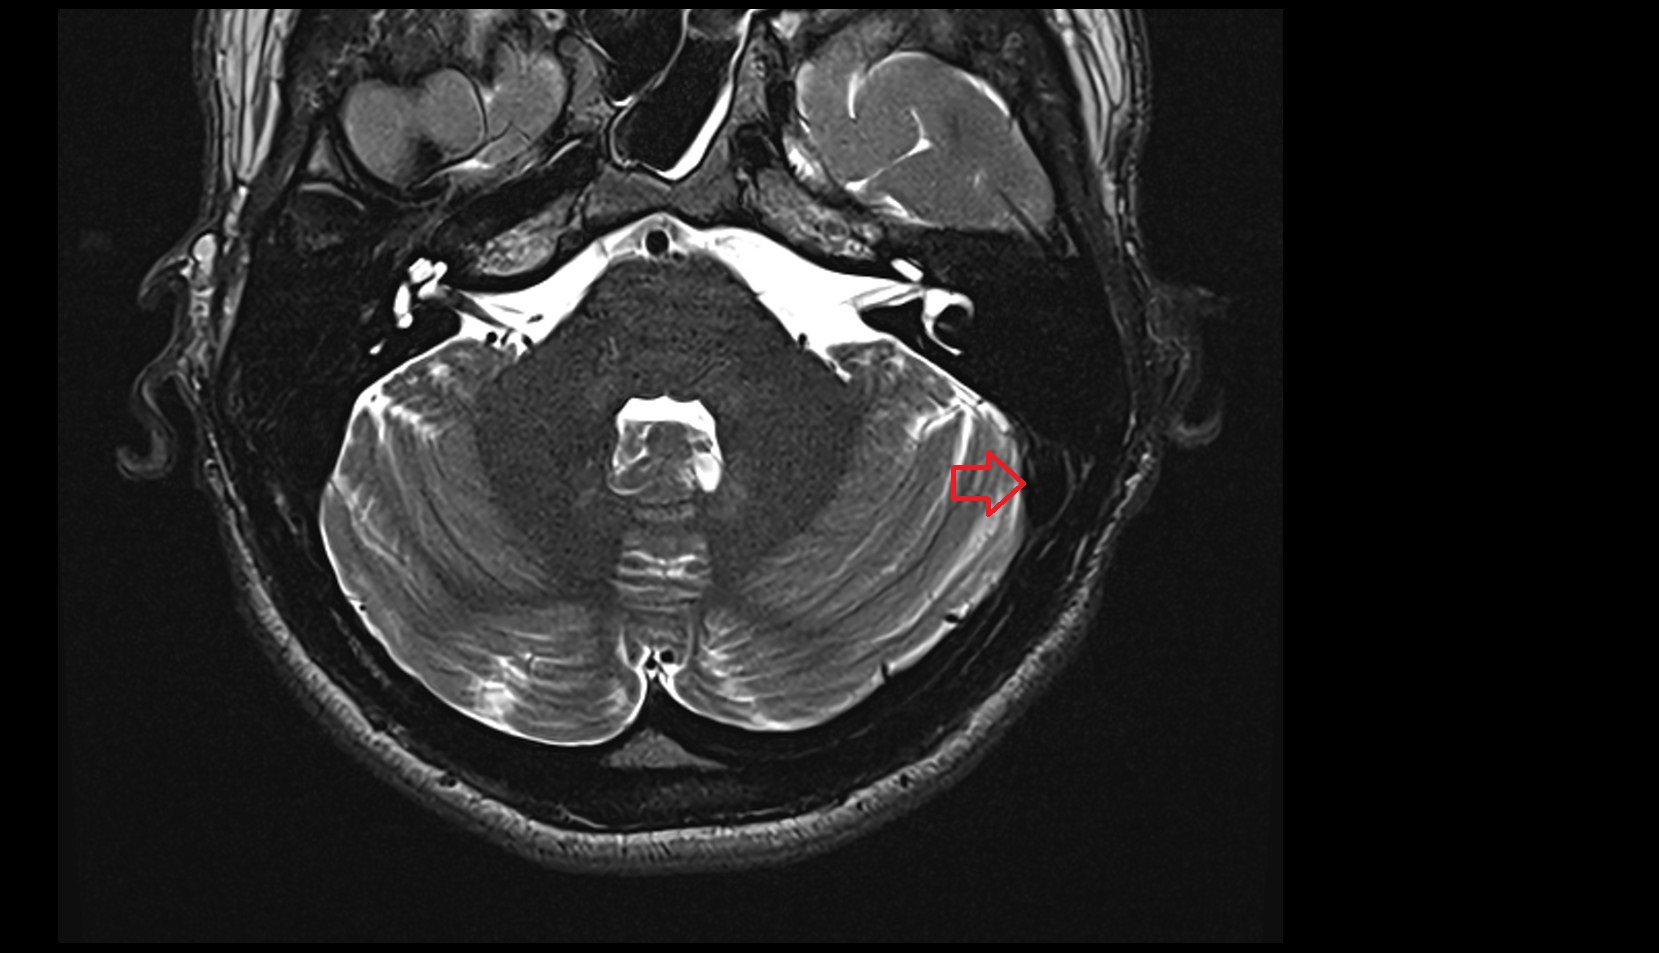

- Flocculus

- Cerebellar tonsil (H IX)